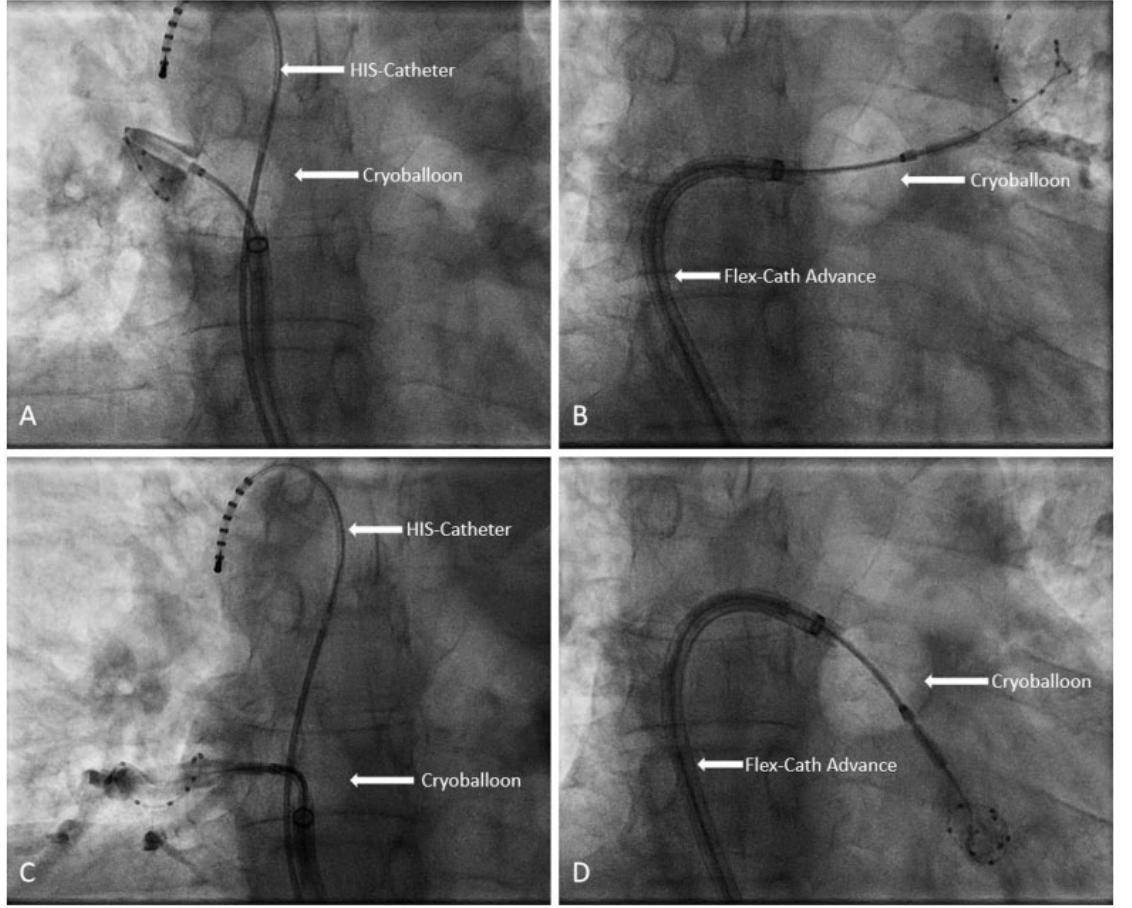

使用 Inoue 二尖瓣成形术扩张器扩张后,SL0-Sheath 成功通过房间隔。左心房的正常解剖结构经血管造影证实,然而,由于心脏轴偏和前颅经中隔穿刺,右侧肺静脉对比较差。右肺静脉的选择性血管造影导致鞘移位回到右心房。重复穿刺后,使用额外强度导丝放置FlexCath advanced鞘。使用Achieve-Catheter和第二代冷冻球囊成功封堵左上肺静脉(LSPV)(图4)。尽管多次尝试,最低温度仅为-26摄氏度。然而,LSPV在第一次冷冻后获得了早期分离。

左下肺静脉(LIPV),相对于经中隔穿刺点位于非典型的后下方。与正常解剖结构相比,肺静脉的位置比预期的更靠后,为了阻塞肺静脉,必须在不典型的后位放置球囊,这使得在一次冷冻和最低温度-42℃的情况下成功阻塞和隔离了LIPV。在消融右肺静脉之前,CS导管被重新定位到上腔静脉,右膈神经的电捕捉良好。由于之前鞘层移位进入右心房,所以首先以右上肺静脉为靶点。由于起搏导管移位导致膈神经的截获性丢失,必须终止第一次冷冻,并重新放置导管。

图3: (A) 透视图像显示右上肺静脉被膨胀的冷冻球囊阻塞。 在图像中可以清楚地看到一个放置在上静脉中的十极 HIS 导管,用于同时刺激膈神经。 (B) 左上肺静脉闭塞。 (C) 右下肺静脉闭塞,同时通过十极 HIS 导管对膈神经起搏。 (D) 左下肺静脉闭塞。

第二次冷冻开始,温度达到-49摄氏度,没有完全隔离;然而,额外的冷冻会导致早期和持续的肺静脉隔离(最低温度-44摄氏度)。最后,右下肺静脉的位置比预期的更差,通过一次冷冻(最低温度-45℃)成功地闭塞和分离(所有肺静脉的冷冻球囊闭塞见图3)。排除围手术期和术后并发症,患者于介入后第二天出院。透视时间30min。剂量-面积积达到1991.7cgycm2。总手术时间110min。在2年的随访(通过电话),病人保持稳定的窦性心律。